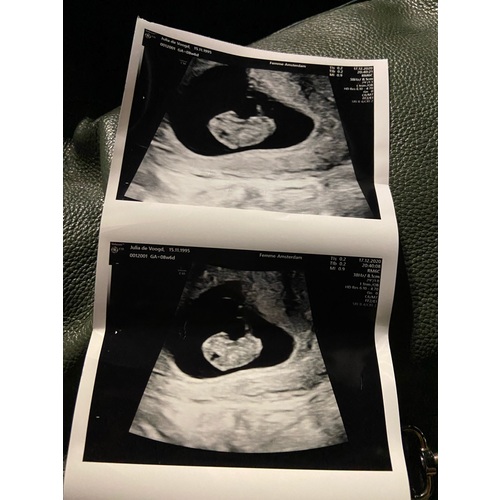

Ik dacht 8 weken te zijn bij de echo ze hadden me alleen iets terug gezet naar 7+4. Nu alweer een goede termijn echo gehad en vandaag alweer 11+4.

Ligt een beetje aan de verloskundige waar je zit. Bij de verloskundige waar ik bij zit is dit een medische echo. De vitaliteits echo. Waar ze kijken of er een gezonde zwangerschap is en of het een een of een meerling is. Dit doen ze vaak tussen de 7 en 9 weken.

Helaas moeilijk tezien gisteren echo gehad ban 8+5 maar mijn baarmoeder ligt nog wat verder naar achter dus niet zn hele helderen echo maar hartje klopt en alles was goed 😍😍